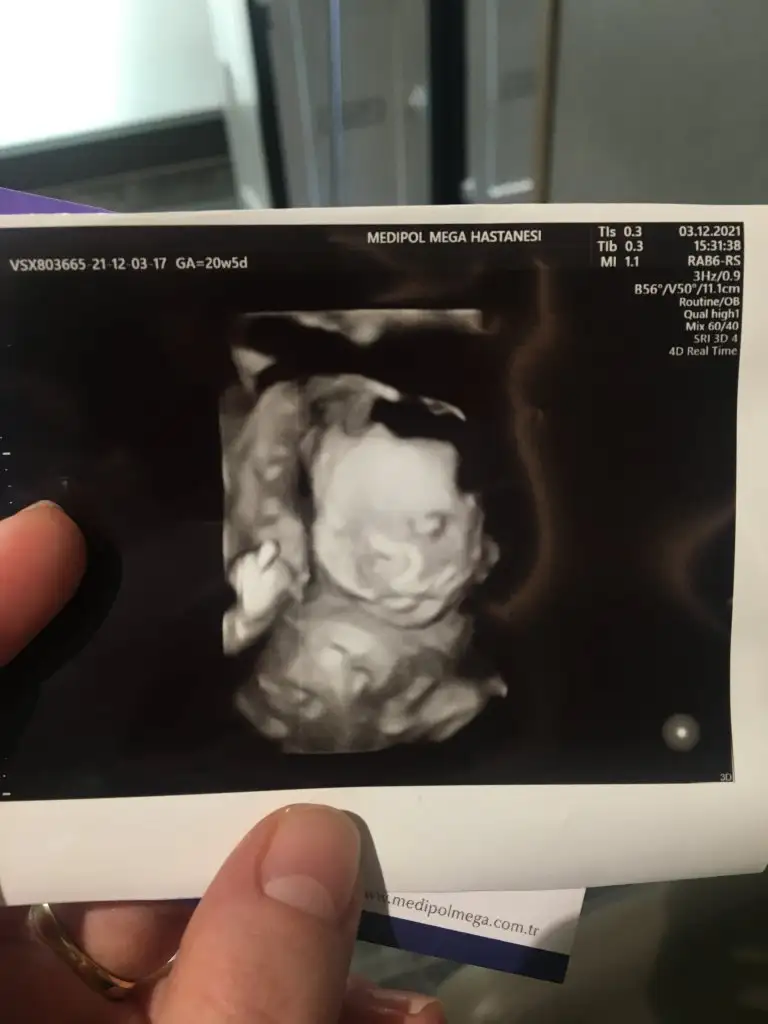

Şükrediyorum ki tekrar ettim detaylıyı ve bu kadar ilgilenildi bugün benimle. 3 kere denedi radyolog sağolsun ara vere vere.